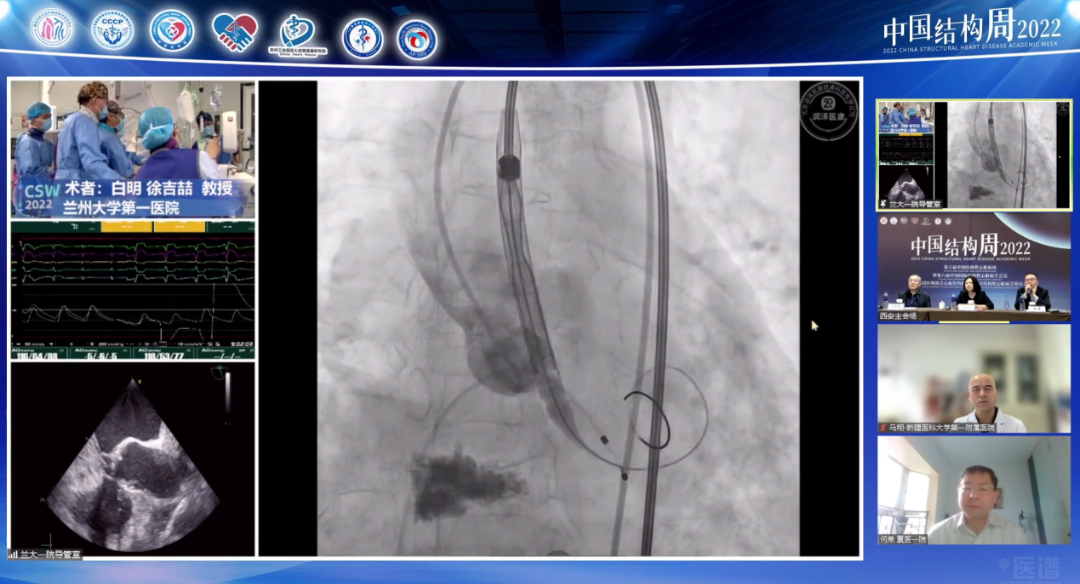

兰州大学第一医院白明教授团队带来一例中重度主动脉瓣狭窄(重度AS)伴钙化,依据患者病情手术策略如下:

Type0型二叶瓣,左右冠脉同窦,瓣叶略增厚,中重度钙化,钙化团块分布于无冠窦底及双侧瓣叶交界处,LVOT偏直筒型,预估瓣膜植入锚定难度适中,受交界处钙化影响,存在瓣周漏可能;

左、右冠高度可,切线位测量,无冗长瓣叶,结合瓦氏窦、STJ内径综合预估,冠脉阻塞风险适中;

左室内径偏小,术中密切关注血流动力学变化,适当补液;

横位心,升主无明显扩张,弓部宽度角度可,预估输送器可顺利过弓备snare在必要时辅助跨瓣,选择TaurusElite输送系统过弓跨瓣性能较佳;

股-髂动脉走行可,内径可,几乎无钙化分布,腹主动脉局部少许钲化分布,以右侧股动脉作为主入路;

跨瓣、球扩、瓣膜植入共同采用双窦展开角度RAO 22 CAU 20左右;

备用角度:左冠切线位LAO O CRA 30。

术中针对球扩瓣size选择、如何预防瓣周瘘、横位心造成的高低瓣等问题展开细致研讨。术中选用18mm球囊预扩张,考虑到患者二叶瓣,依据瓣环而不是瓣上结构选择瓣膜大小,瓣膜选择瓣叶展开较好的球扩瓣downsize,其不容易下滑稳定性较好。术后造影显示高低瓣,少量反流,血流动力学很好,主动脉瓣峰值流速1.5m/s。术后分析反流原因可能是左冠瓣裙边位置在流出道,造影剂通过网眼流出,但若选择大一些瓣膜,瓣膜移位可能性相应会增加,故术后随时关注瓣膜展开情况,若瓣叶对合没问题少量反流可以接受。